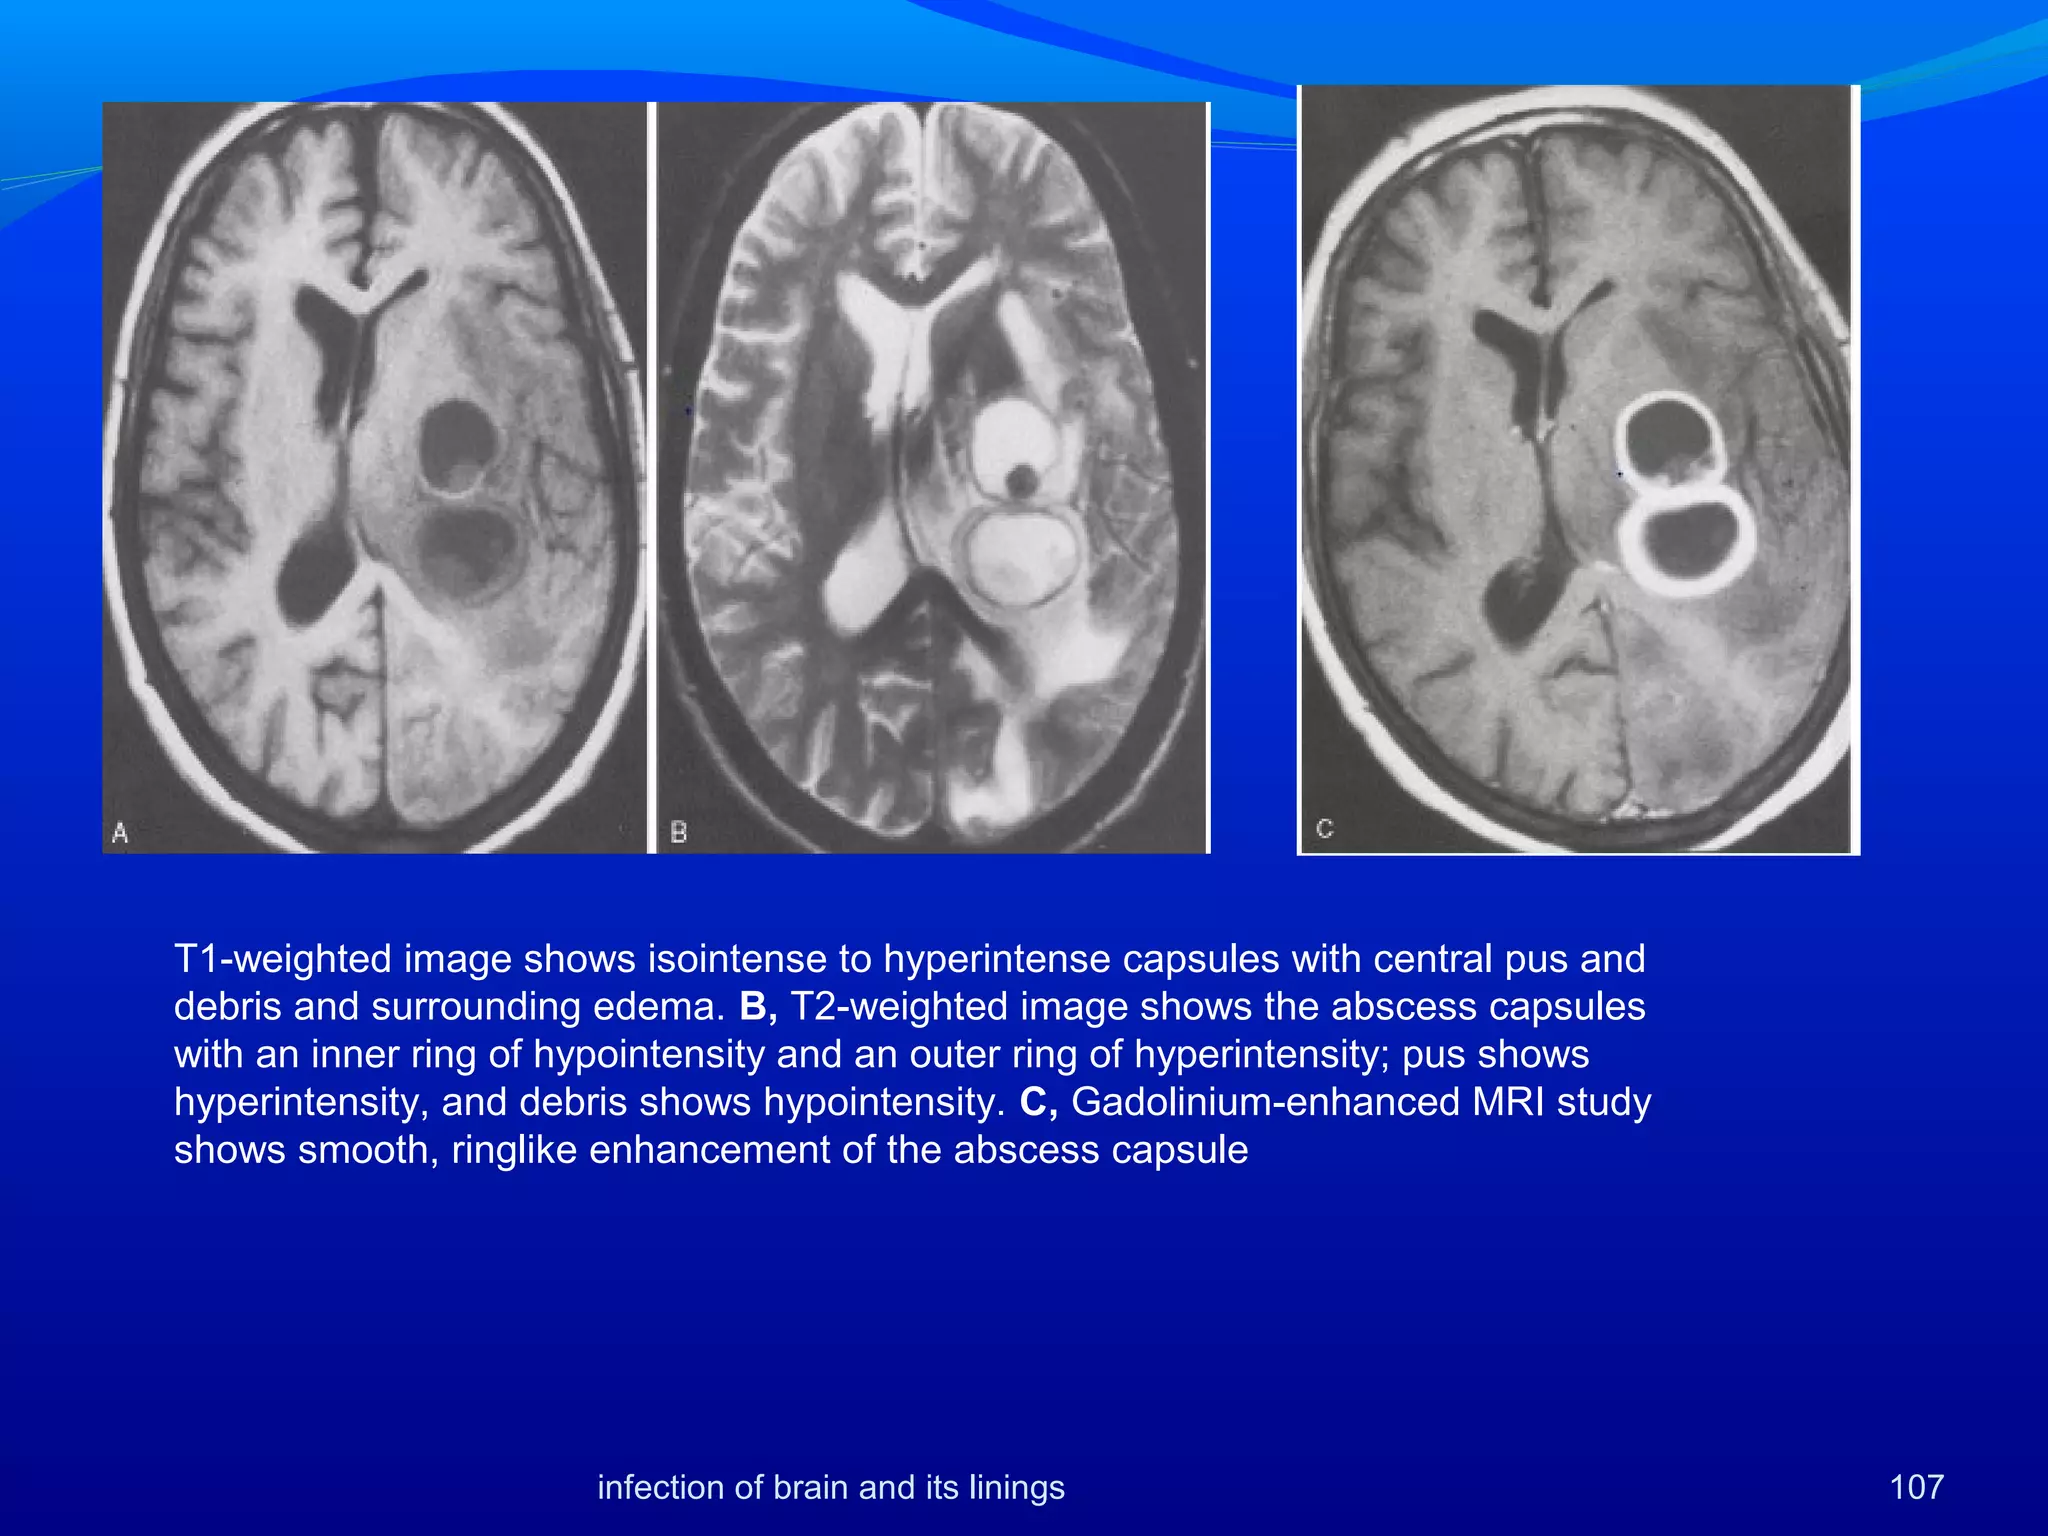

107

T1-weighted image shows isointense to hyperintense capsules with central pus and

debris and surrounding edema. B, T2-weighted image shows the abscess capsules

with an inner ring of hypointensity and an outer ring of hyperintensity; pus shows

hyperintensity, and debris shows hypointensity. C, Gadolinium-enhanced MRI study

shows smooth, ringlike enhancement of the abscess capsule